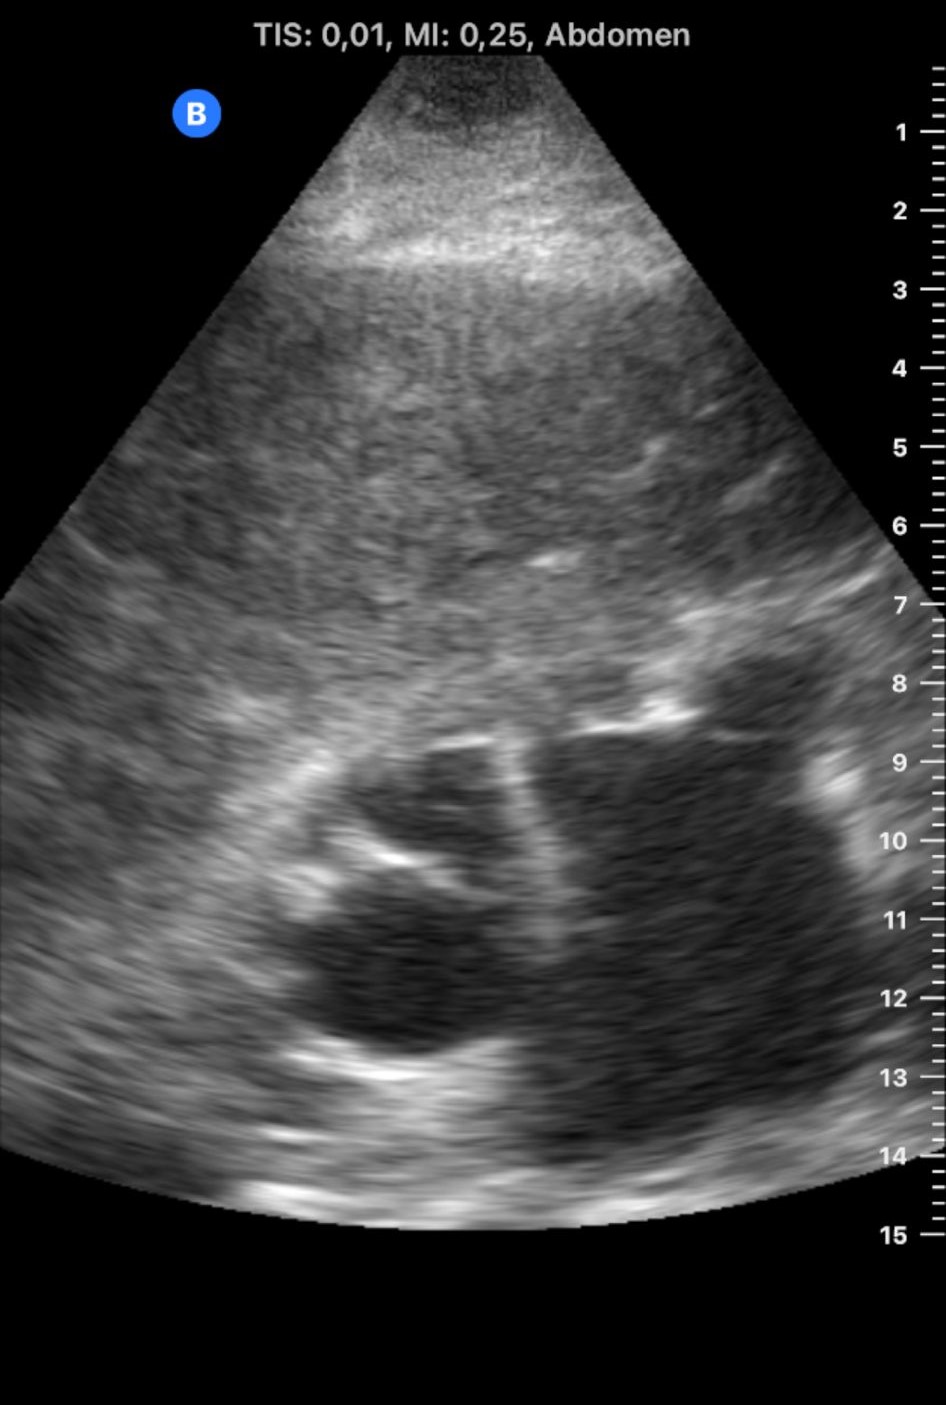

Se lleva a cabo una ecografía abdominal a pie de cama que evidencia ambos riñones de tamaño y localización normal. Relación corticomedular no conservada de riñón derecho debido a hidronefrosis grado IV, sin litiasis visible.